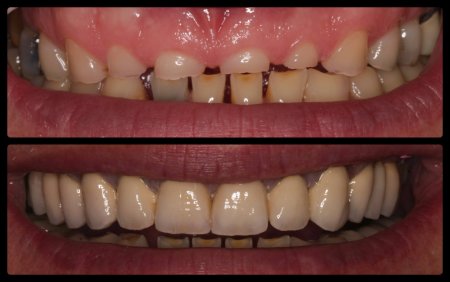

ΠΡΟΣΘΕΤΙΚΕΣ ΑΠΟΚΑΤΑΣΤΑΣΕΙΣ ΜΕ ΣΥΝΔΥΑΣΜΟ ΛΕΥΚΑΝΣΗΣ, ΣΥΝΘΕΤΩΝ ΡΗΤΙΝΩΝ ΚΑΙ ΟΛΟΚΕΡΑΜΙΚΩΝ ΟΨΕΩΝ ΚΑΙ ΣΤΕΦΑΝΩΝ